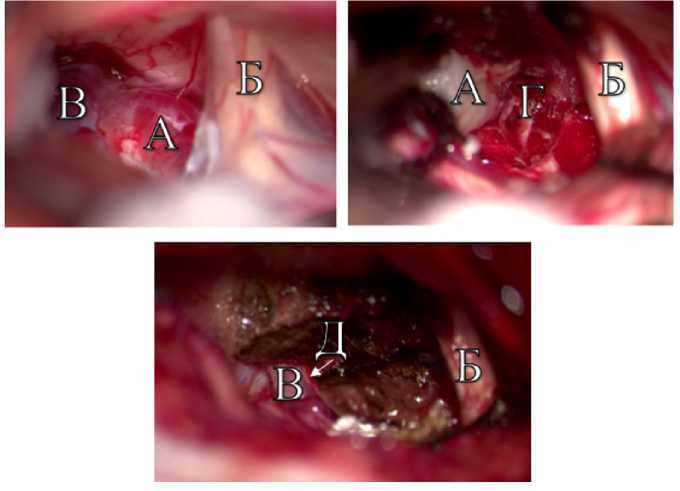

Операция выполнена в положении «лежа» на спине с поворотом головы влево. Проведено тотальное удаление опухоли из ретросигмовидного доступа (рис. 5).

Рис. 5. Интраоперационные снимки удаления опухоли в ЗЧЯ пациента О. А — невринома тройничного нерва; Б — акустико-фациальная группа нервов; В — верхняя каменистая вена; Г — отводящий нерв; Д — волокна тройничного нерва

Fig. 5. Intraoperative images of tumor removal in the PCF of patient O. A — trigeminal neuroma; Б — facial acoustic nerve group; B — superior petrosal vein; Г — abducens nerve; Д — trigeminal nerve fibres